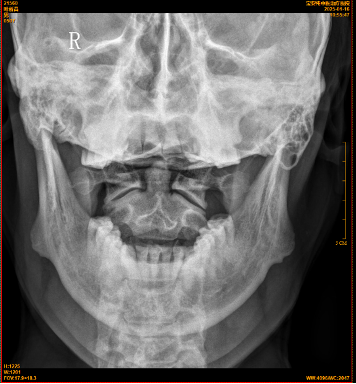

【影像】20250117颈椎X线片报寰齿间距略失对称,颈椎退行性变,C4椎体稍后移。阅片见颈椎上段平直,C4-5失稳,C2-3、C5-6前缘增生,项韧带钙化,右侧寰枢外侧关节对合不全,枢椎棘突略偏左。

【讨论】患者颈及枕部疼痛,颈椎左旋受限;查体C1左侧横突、C2右侧横突压痛(+),右侧头后大直肌紧张、压痛(+);X线片报寰齿间距略失对称,

阅片见右侧寰枢外侧关节对合不全,枢椎棘突略偏左;诊断为寰枢关节半脱位。时有头晕、头痛,考虑与本病相关。